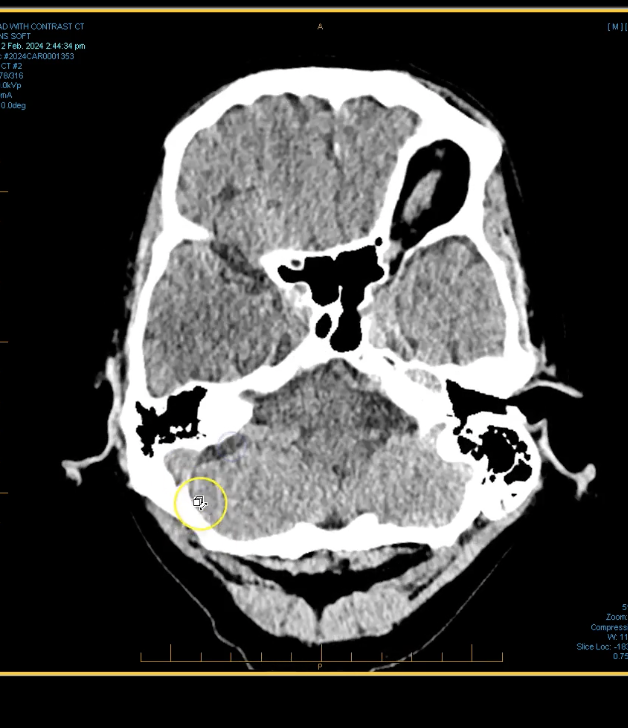

term image

pons